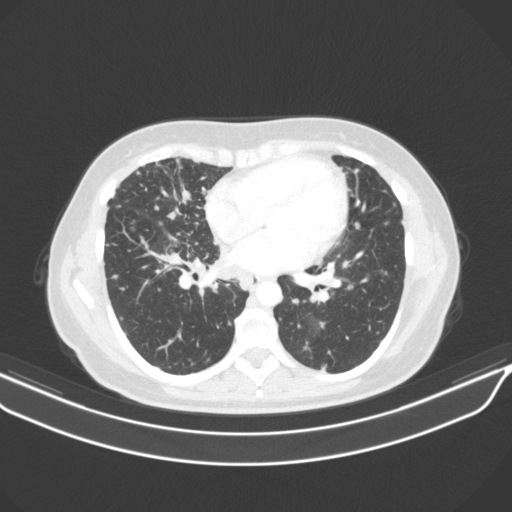

Original VENOUS CT scan

No window - Raw intensity values

Lung window (WL -600, WW 1500 β†’ Low βˆ’1350, High +150)

Targeted Slice 70 - Lung Window Analysis (Generated vs Real Venous)

0.752

Lung SSIM

110.9

Lung RMSE

46.5

Lung MAE

Average Lung Window Metrics Across All Slices (133 slices) - Generated vs Real Venous

0.749

Lung SSIM (Avg)

109.7

Lung RMSE (Avg)

44.6

Lung MAE (Avg)